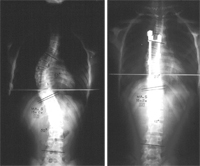

La cirugía es el último recurso en el tratamiento de la escoliosis. Afortunadamente es el tratamiento que necesitan menor número de enfermos. La indicación para la cirugía es en curvas torácicas de 45 a 50º con evidencia considerable de progresión después de terminar el crecimiento.

- ¿En qué consiste la intervención?

El procedimiento quirúrgico más frecuente para corregir la escoliosis idiopática del adolescente es una fusión posterior con instrumentación e injerto óseo, y el objetivo será conseguir una corrección parcial de la curva ahorrando el mayor número de vértebras a fusionar, con el fin de obtener una columna estable y equilibrada. Generalmente no es necesario el uso de corsés tras la cirugía, los enfermos andan al segundo o tercer día y vuelven a realizar las actividades diarias o habituales en un periodo de tiempo muy breve. Las complicaciones son muy infrecuentes.